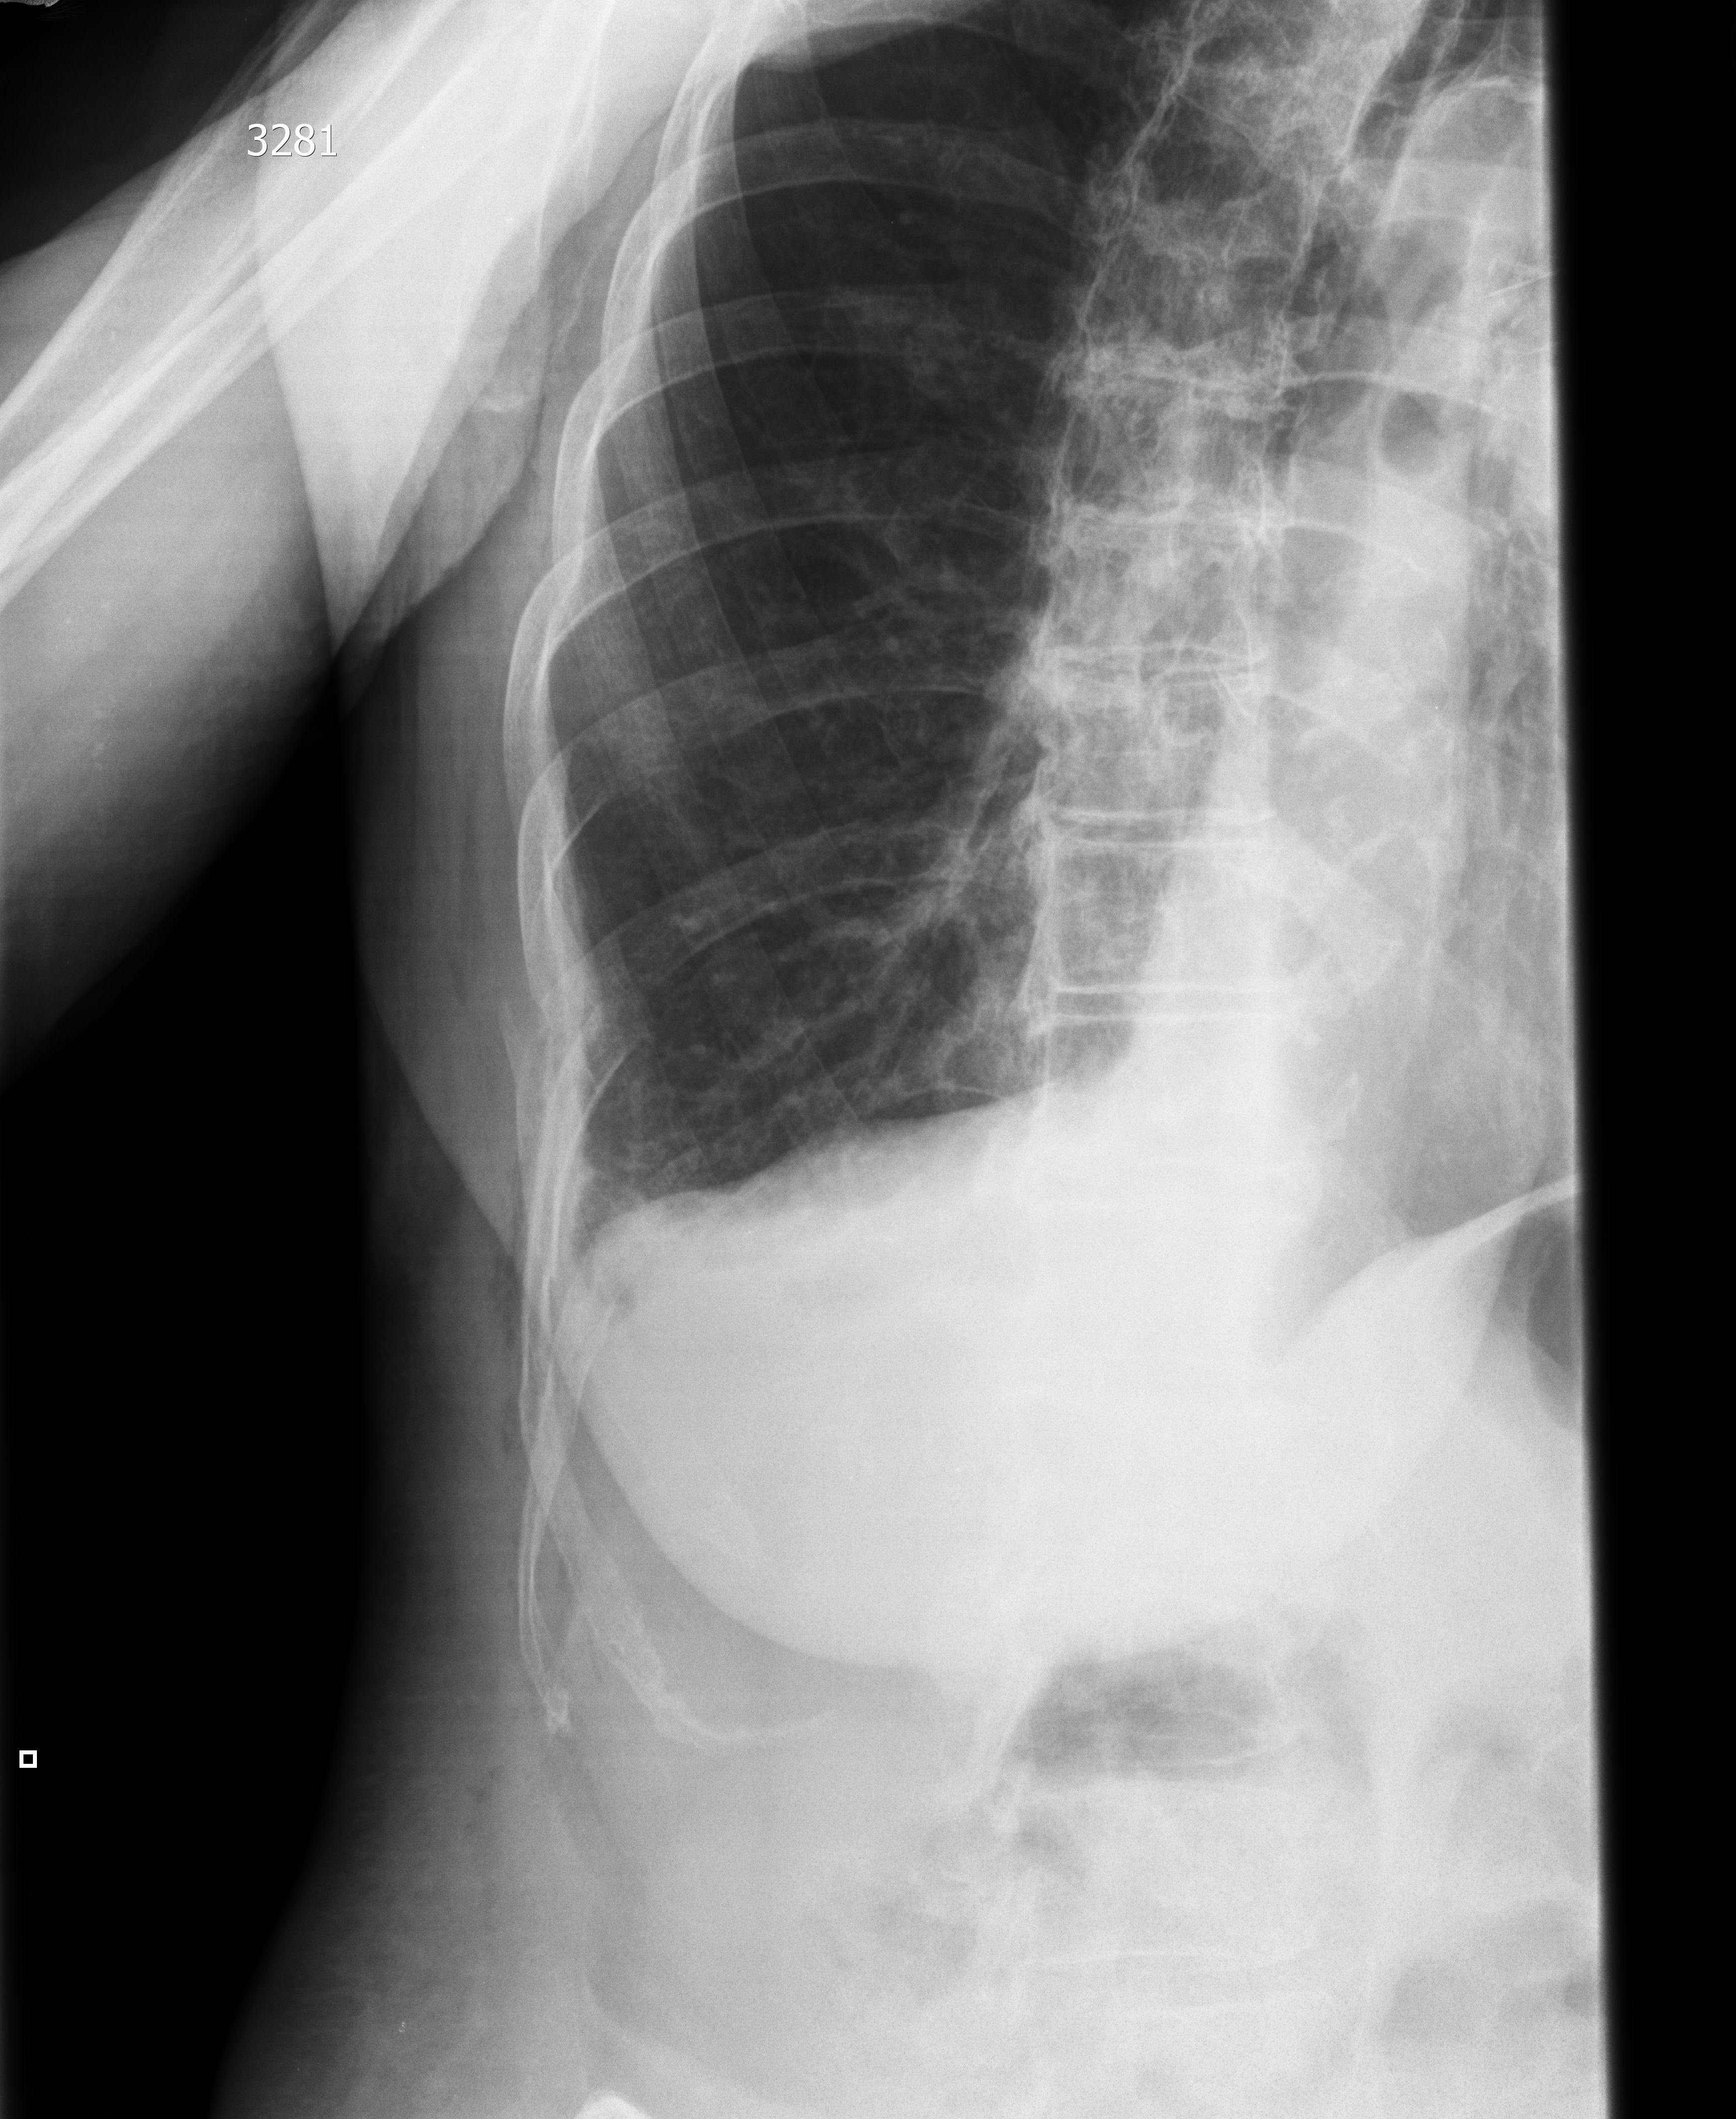

Пожилая женщина, ударилась об угол стола.

Рентгенологически описан только перелом X ребра справа.

При УЗИ имеются признаки перелома X и IX ребер (IX - оскольчатого), подкожной эмфиземы, пневмонии и плеврита.